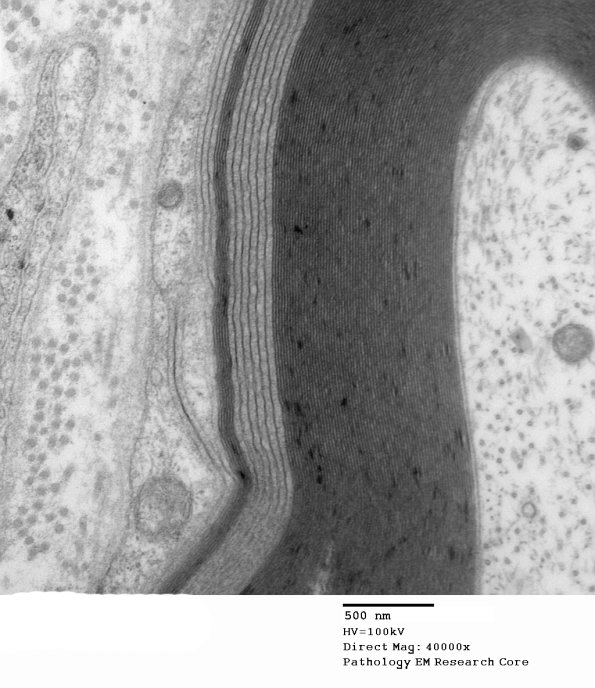

Several magnifications of WSM showing marked differences in periodicity of myelin. (electron micrographs)